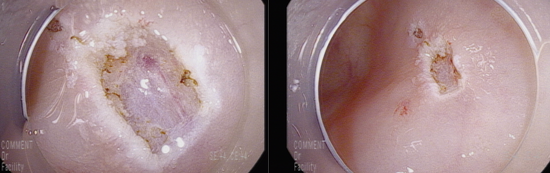

점막암 이상의 병변을 의심하여 충분히 융기시킨 후 근위부에 snare를 anchor할 hole을 만든 후 충분히 잡아서 육안적 완전 절제함

조직학적 침범 여부/정도 확인이 필요함.

조직검사는 저등급의 선종으로 확인됨.

Colon, 9cm from anal verge, colonoscopic polypectomy;Tubular adenoma with mild to moderate dysplasia (low grade dysplasia)* resection margin: Negative(-)